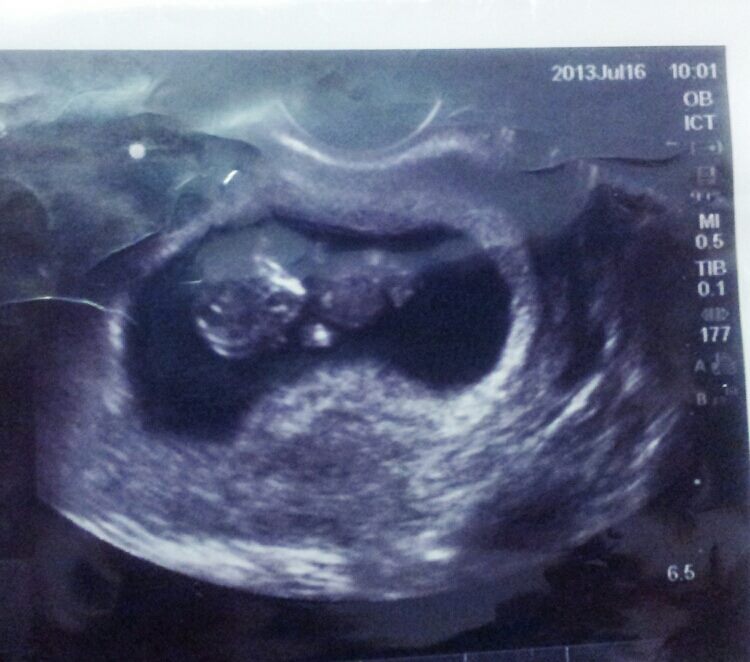

Now for the amazing news! My son sent us a package and said we couldn’t open it until we skyped with him and his lovely wife. This is what was inside:

How amazing is that? I am still in shock! This will be our first grandchild and frankly, I think I am much too young …..how did my son get to be old enough to be a dad himself? So my hubby and I have been saying that “grandma and grandpa” sound old…and we don’t want to be confused with the other grandparents so we need to figure out what this beautiful child will call us. What do your grandchildren call you?

And here is my first gratuitous grandbaby picture:

You can see already that this child is beautiful, smart, incredible!